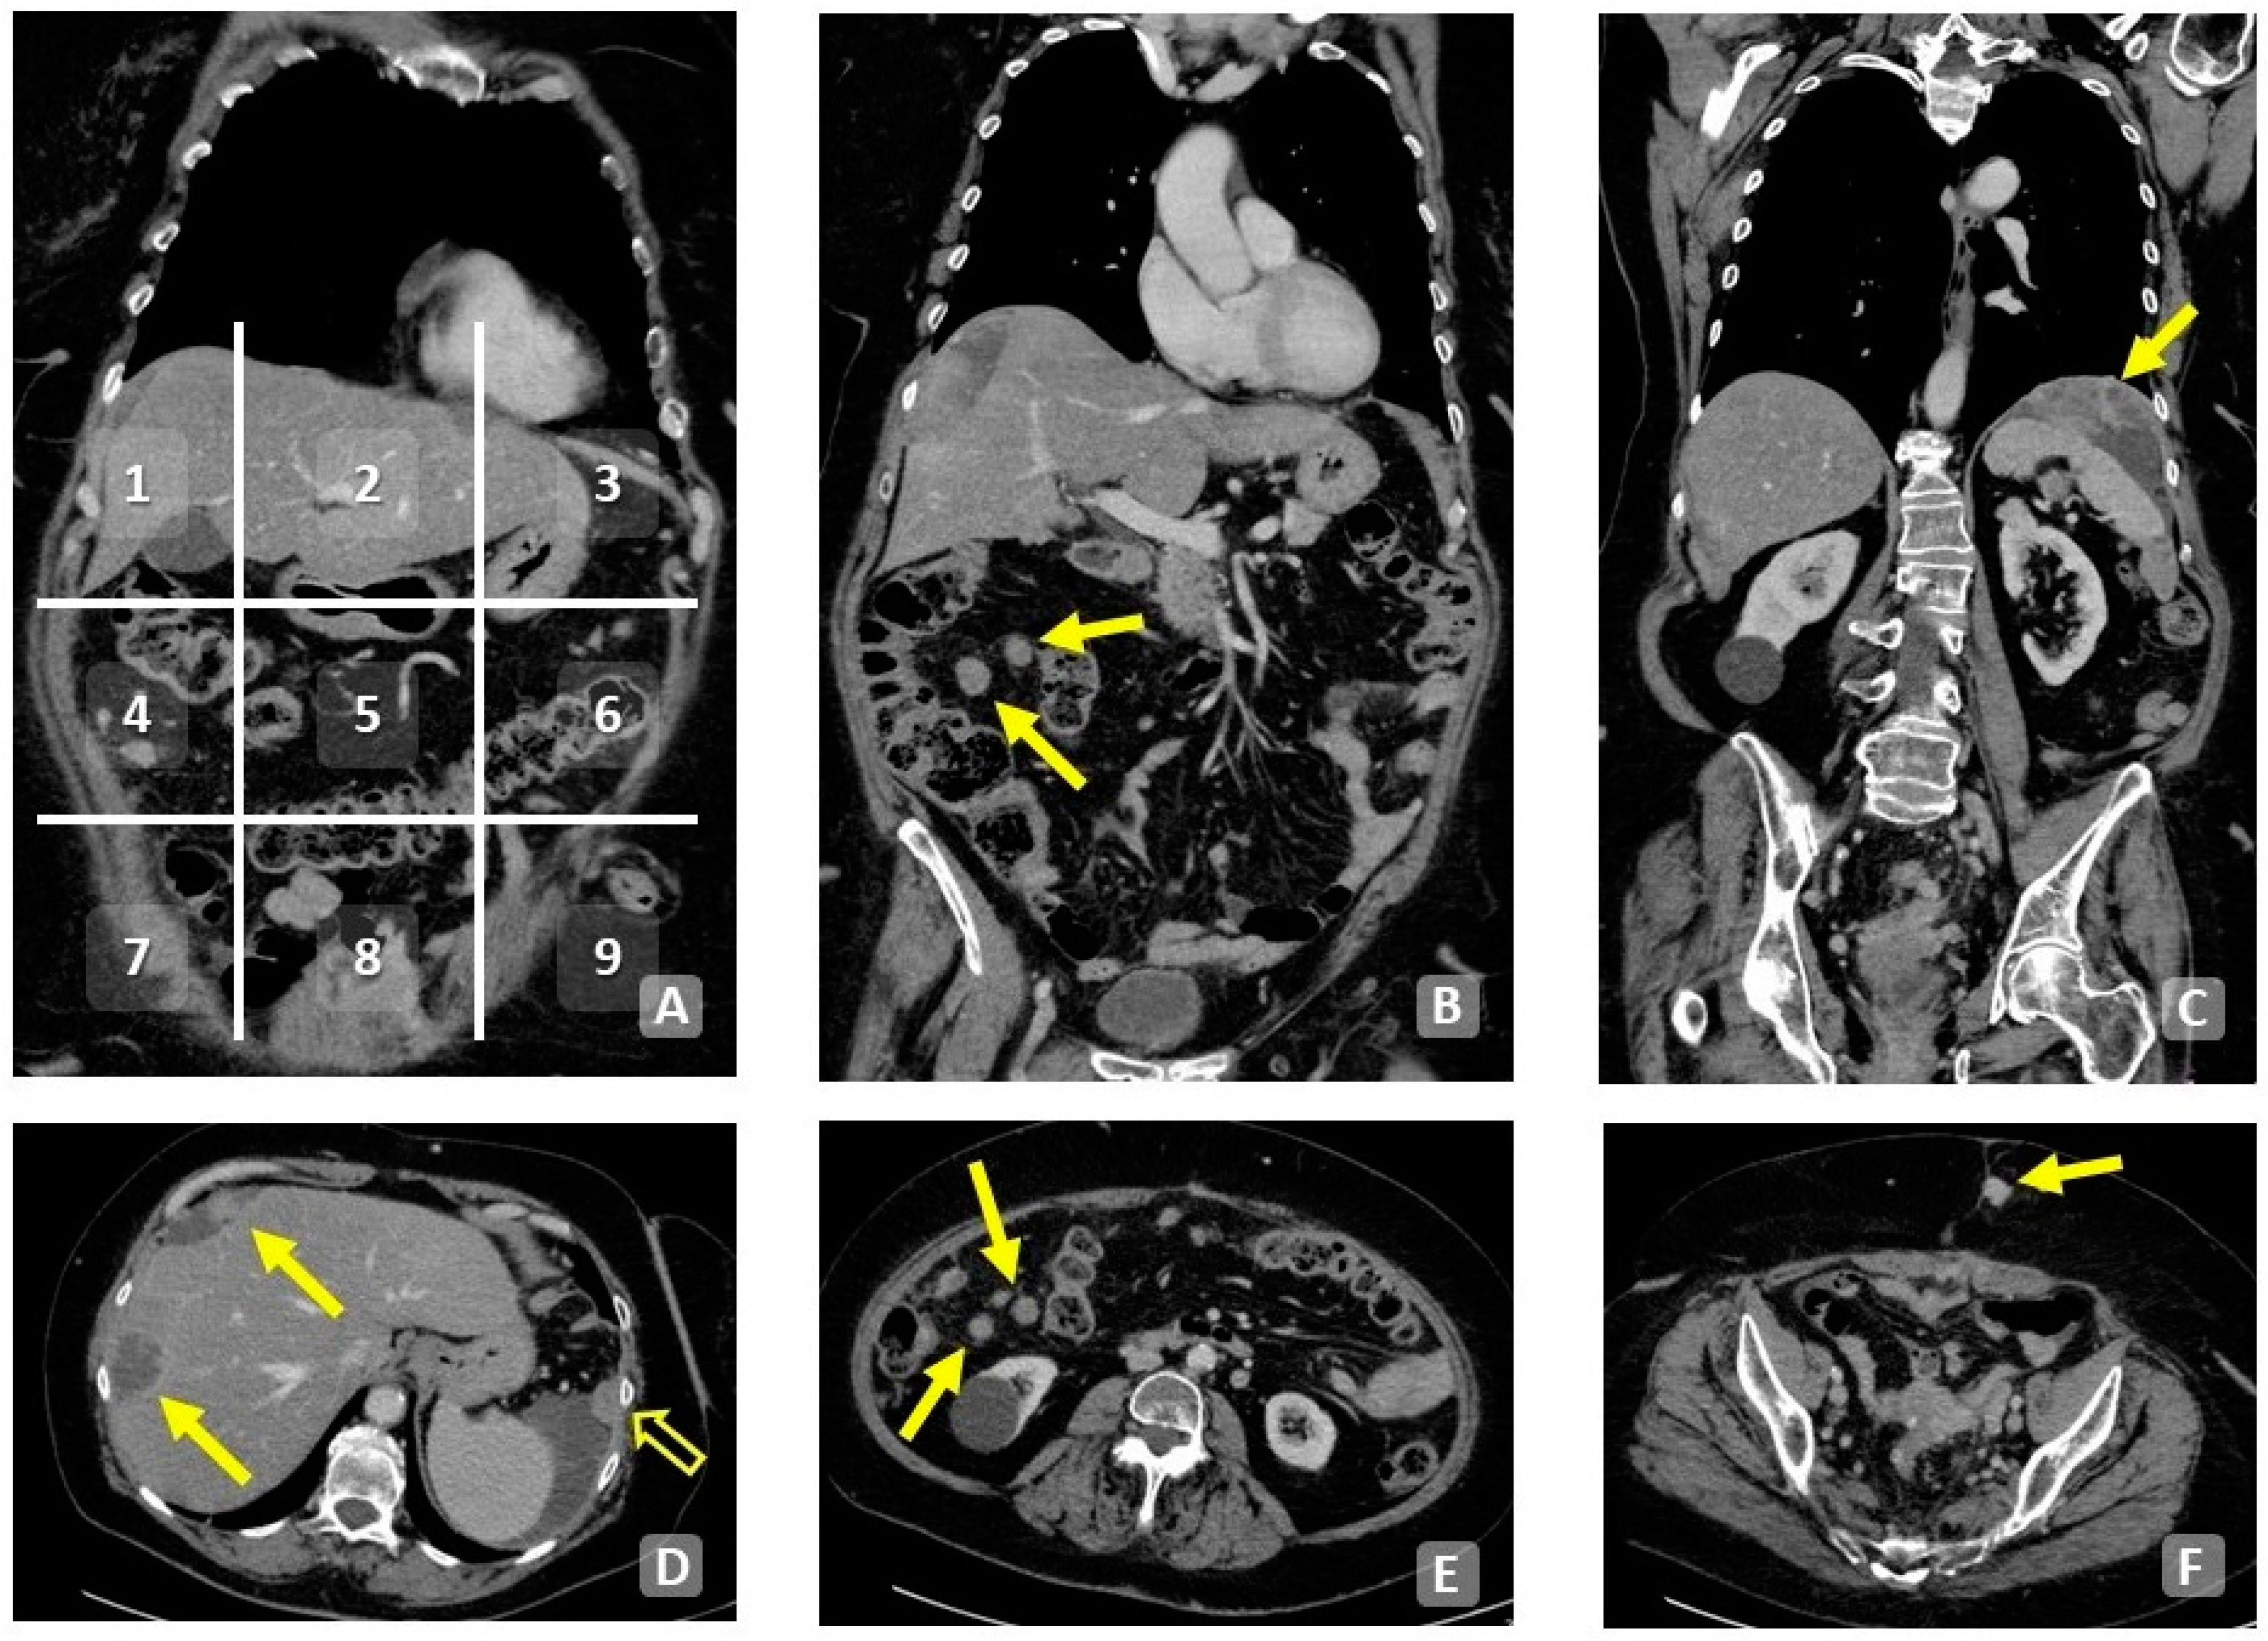

7. Scoring System in Diagnostic Imaging

7.1. Peritoneal Cancer Index (PCI)

7.2. Bowel, Upper Abdomen, Mesentery in Peritoneal Metastasis (BUMPY)